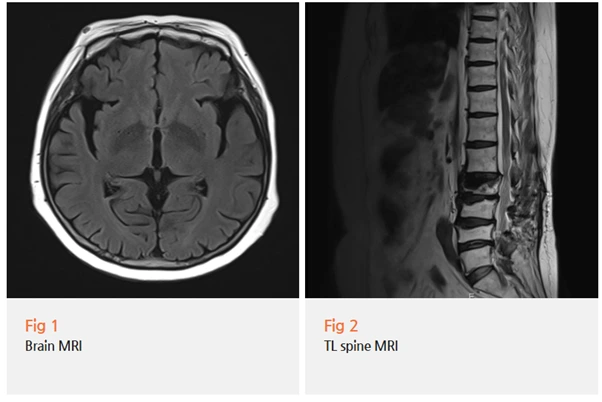

타병원에서 뇌 MRI, MRA 검사를 다 했지만

"이상 없다"는 소견만 받으셨다고 하더라고요.

그래서 정밀 검사를 진행했어요.

신경과 협진을 통해 뇌 MRI를 다시 시행하고,

파킨슨병에 특화된 추가 검사들을 진행했습니다.

그리고 결과는...

파킨슨병이었어요.

게다가 MRI 찍어도 초기엔 잘 안 나와요.

파킨슨병은 뇌 속 도파민 신경세포가 서서히 죽어가는 병인데,

MRI로는 이런 미세한 변화를 초기에 포착하기가 어렵거든요.